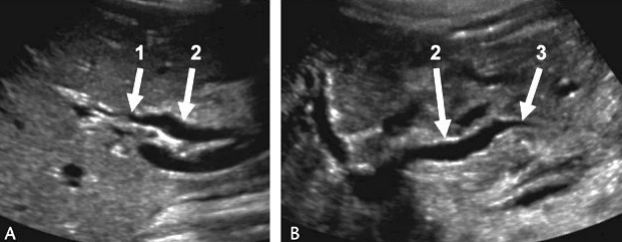

Acute pancreatitis with stone obstructing the pancreatic duct

Describe this image

Diagnosis?

Gallbladder with wall thickening and a stone obstructing the common bile duct causing dilatation (posterior shadowing). Results in pancreatitis

Dx: gallstones/pancreatitis